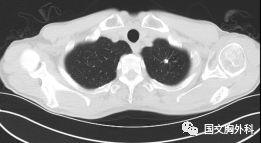

這個(gè)病人檢查胸部CT如圖3:根據(jù)影像學(xué)考慮是惡性腫瘤,行手術(shù)治療后病理回報(bào):“肺膿腫,合并炎癥纖維組織增生”,因此“肺占位”不代表就是惡性腫瘤,診斷金標(biāo)準(zhǔn)是病理診斷。如果檢查后發(fā)現(xiàn)“肺占位”先不要驚慌,及時(shí)就診請(qǐng)專科醫(yī)生會(huì)診指導(dǎo)治療才是關(guān)鍵。